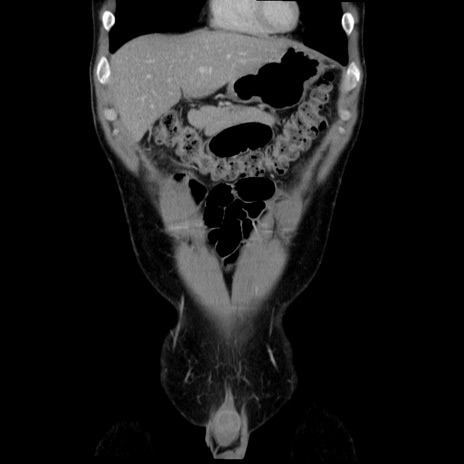

症例36(冠状断像)

【症例】20歳代 男性

【主訴】心窩部痛

【現病歴】今朝より上腹部痛あり。一旦軽快していたが再度出現したため救急要請。昨日夕に白身の魚を含む刺身を食べた。

【身体所見】BP 136/89mmHg、HR 74/min、BT 37.0℃、腹部:膨満、軟、心窩部に圧痛あり。反跳痛なし、筋性防御なし、腸雑音やや亢進あり。

【データ】WBC 17700、CRP 0.48